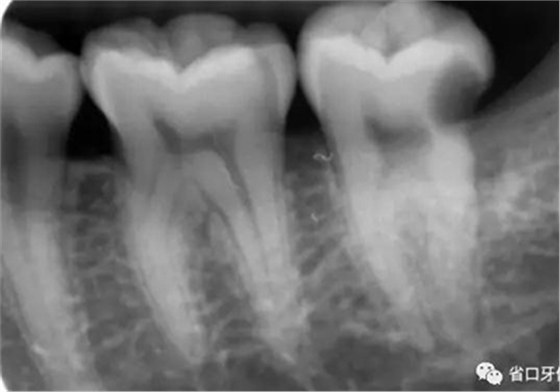

臨床檢查:37遠(yuǎn)中鄰面探及深齲洞,探痛明顯,叩-,無松動(dòng),冷刺激痛明顯,去除刺激后疼痛延遲。X片示37遠(yuǎn)中鄰面牙體低密度影累及髓角。

圖2 術(shù)前X片示遠(yuǎn)中鄰面牙體低密度影累及髓角